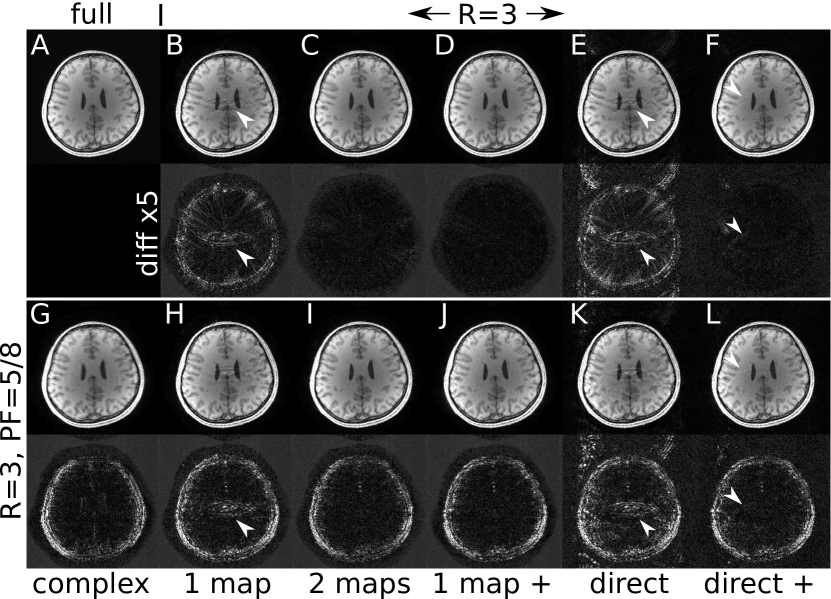

Figure 4: Reconstruction from fully-sampled data (A) and iterative parallel imaging reconstruction (R = 3, 24x24 ACS lines) with (top, B-F) and without (bottom, G-L) additional partial-Fourier sampling (PF=5/8). Sensitivities were estimated with VCC-ESPIRiT using one set of maps (1 map, B,H,D,J) or two set of maps (2 maps, C,I) or directly from the k-space center (direct, E,F,K,L). Some variants use regularization of the imaginary component (indicated by ++, D,J,F,L) or no phase constraint (complex, G). If the high-frequency phase of the image is not correctly modelled, a real-value constraint causes artifacts (arrows). Difference images to the fully-sampled reference are scaled up by a factor of five.

Figure 4 demonstrates reconstruction of data from an accelerated parallel-imaging and a parallel-imaging partial-Fourier acquisition using differently estimated maps and various constraints. When using a single set of maps together with a real-value constraint, aliasing artifacts are not completely resolved in the reconstruction (B,E,F,H,K,L). By using a second set of VCC-ESPIRiT maps the real-value constraint is relaxed in image regions affected by high-frequency phase. In this example, this yields reconstructions almost without visible artifacts (C,I). Good reconstructions can also be obtained when the real-value constraint is generally replaced by regularization of the imaginary component (D,J). Comparing the results using VCC-ESPIRiT maps with results using directly estimated maps (EF,KL) confirms the better accuracy of ESPIRiT maps. Even when using regularization of the imaginary part minor artifacts remain in the case of directly estimated maps. For the partial Fourier case, the iterative reconstruction without real-value constraint shows pronounced blurring due to the missing information in one half of k-space (G). Using a real-value constraint or regularization of the imaginary part yields sharp images (H-L).